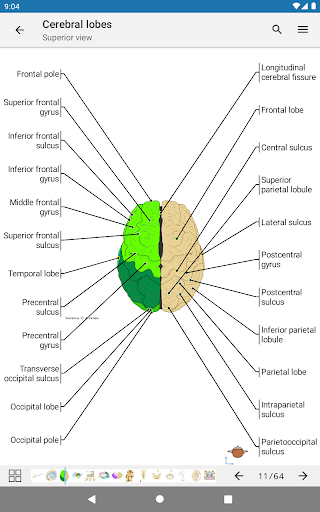

e-Anatomy tiene más de 26 000 imágenes que contienen series de imágenes en vistas axiales, coronales y sagitales, así como radiografías, angiografías, imágenes de disección, gráficos anatómicos e ilustraciones. Todas las imágenes médicas fueron etiquetadas cuidadosamente, más de 967 000 etiquetas disponibles en 12 idiomas, incluida la Terminologia Anatomica latina.

- Toque las etiquetas para mostrar las estructuras anatómicas

- Seleccione las etiquetas anatómicas por categoría